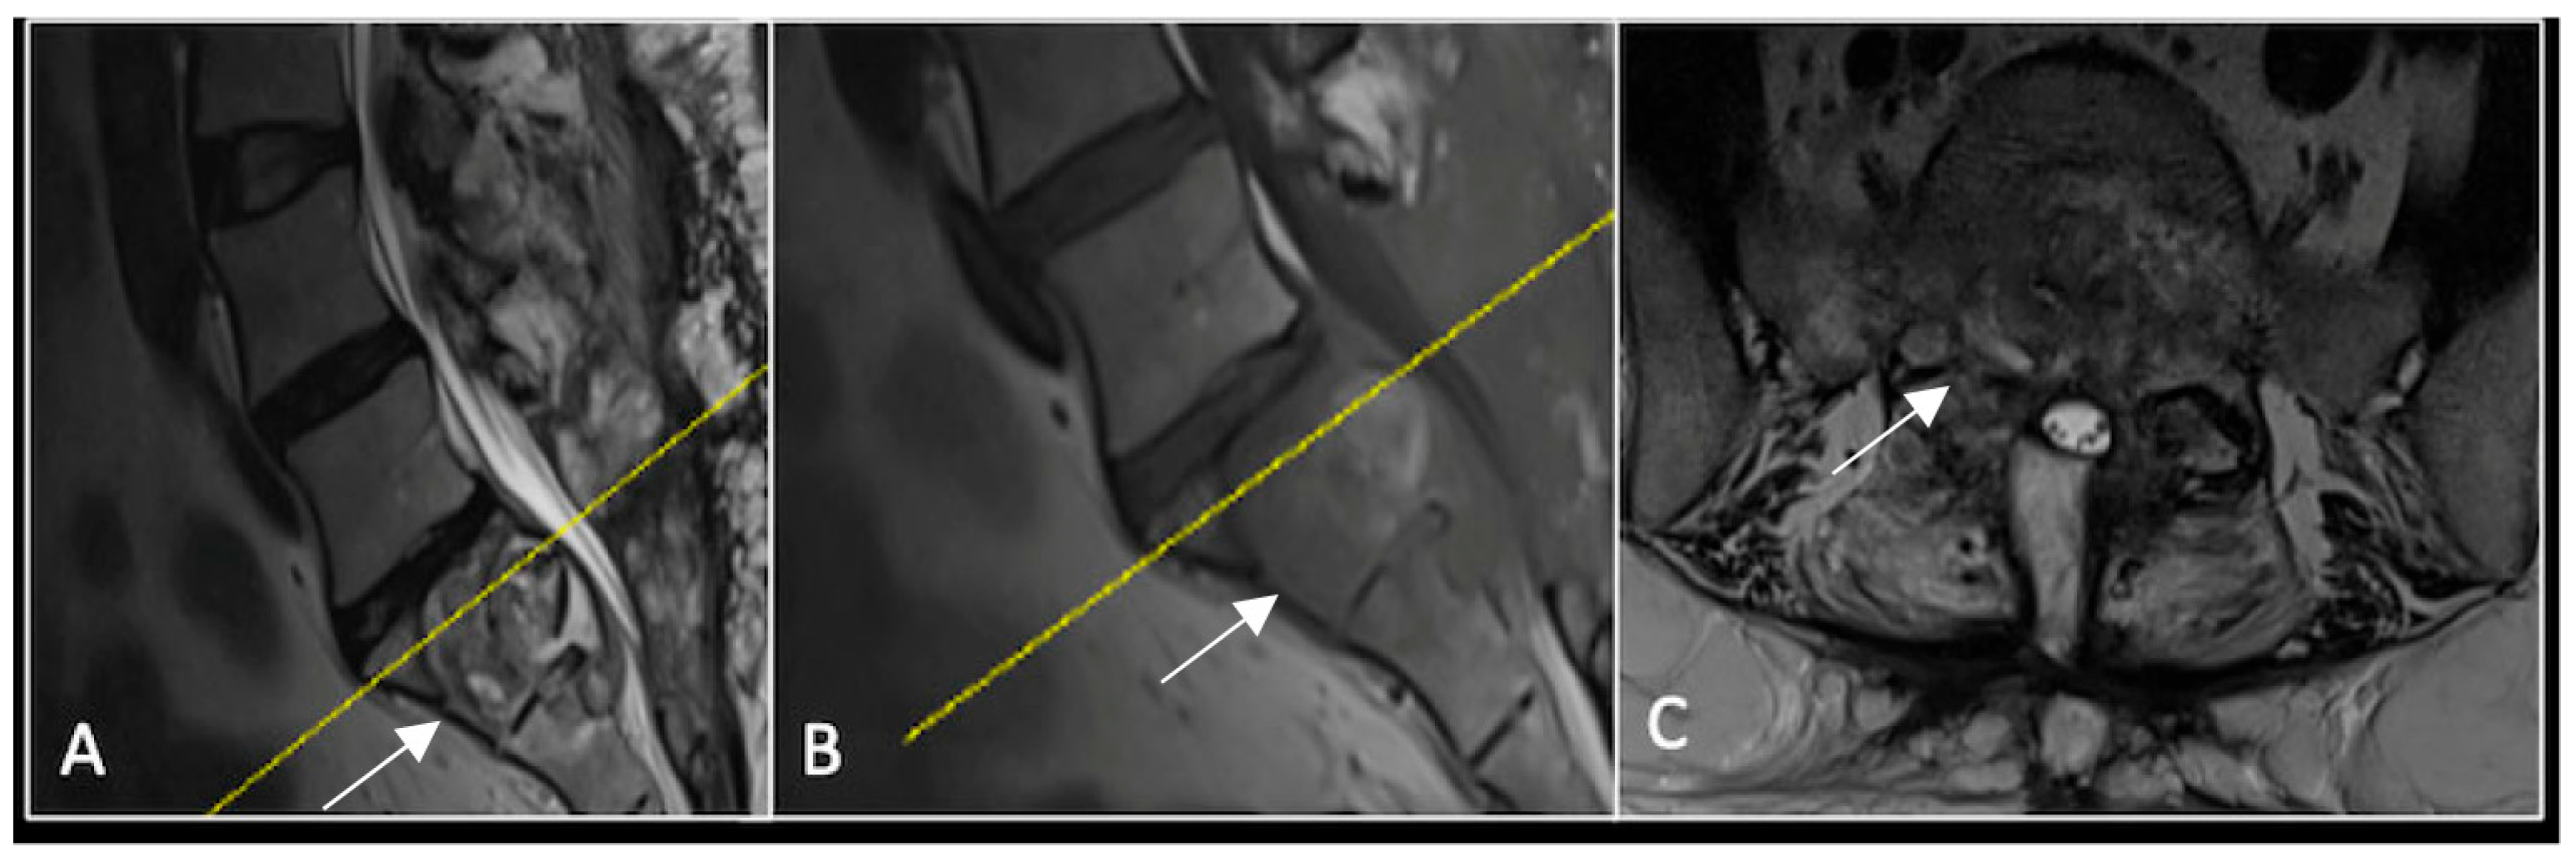

This 63-year-old male presented with sacral pain and right-sided S1 radiculopathy. He was subsequently referred to our institution after diagnostic imaging revealed a destructive lesion within the S1 vertebra (Figure 4). The patient developed symptoms of acute cauda equina syndrome, for which we recommended an emergent surgical decompression to be performed at the referring hospital. Biopsy confirmed a conventional chordoma. The patient chose to undergo separation surgery, given the significant morbidity associated with an en-bloc sacral resection, including sacrifice of the neural structures innervating his bladder and bowel. He received adjuvant proton beam therapy, and 6-monthly surveillance imaging revealed stable disease (Figure 5). Unfortunately, 12 months post-separation surgery, there was evidence of tumour progression with epidural extension and symptomatic deterioration in bladder function, requiring revision surgical debulking (Figure 6).

Figure 4.

MRI demonstrating a destructive lobular sacral mass (arrow) with invasion of the S1 vertebral body and complete compression of the cauda equina neural elements. The yellow line on the axial image represents the plane of the corresponding axial section. (A) T2W sagittal; (B) T1W sagittal; (C) T2W axial.